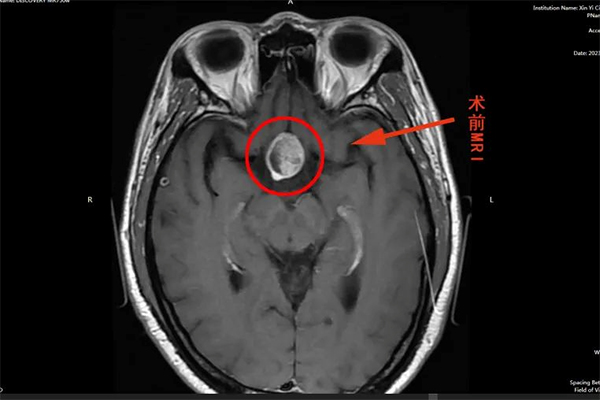

▲ 術前頭部MRI

陸先生因無明顯誘因突發(fā)頭痛眩暈不適,伴頭暈、頭脹、惡心、嘔吐癥狀,急來中醫(yī)院神經(jīng)外科謝宏剛團隊處就診。頭部MRI示:雙側(cè)篩竇粘膜肥厚,有23×20×36mm垂體大腺瘤。符合手術指征,在與家屬溝通后進行了充分的病情討論后,謝宏剛團隊決定為患者行“神經(jīng)內(nèi)鏡下經(jīng)鼻—蝶竇垂體病損切除術”。

謝宏剛主任針對患者病情進行了詳細分析,認為垂體腫瘤位置深,臨近視神經(jīng)、海綿竇等重要結(jié)構(gòu),手術風險和難度比較大,預先與團隊分析了術中可能存在的風險及處理方案,在做好了充分的準備后,歷時4小時,成功為患者進行手術,術后復查CT手術效果滿意,不日即可出院。